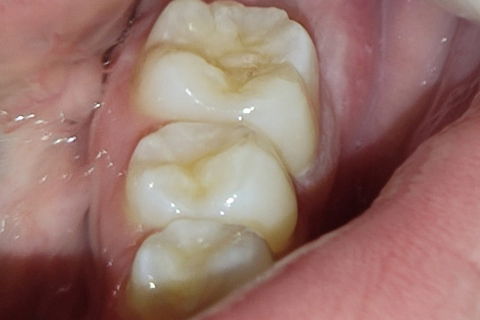

Região do 37/38